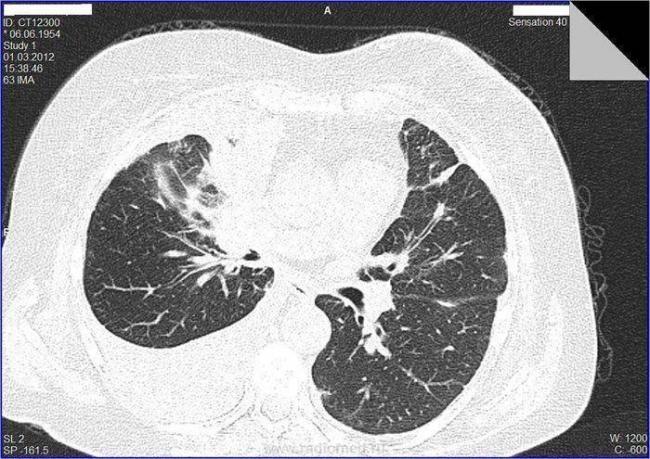

Целесообразна ли операция при моем диагнозе или возможно альтернативное лечение? Евгений Федорович. В августе 2017 года я прошла флюорографию, которая показала затемнение во втором сегменте легкого. Осмотра в мае 2017. Прошла лечение от пневмонии, последующий снимок показал наличие этого же затемнения без изменения. Результат прохождения первого РКТ 10 октября 2017г.:

Средостение расположено в типичном месте, в размерах не увеличено, с четкими контурами, обычной формы, без очаговых патологических образований.

В паренхиме S1-S2 сегментов верхней доли правого легкого определяются гетерогенные интертисциальные изменения за счет полиморфных очагов, размером от 8,5 мм до 44,1 мм в поперечнике, на фоне которых визуализируются участки уплотнения по типу матового стекла

В других сегментах паренхима без очаговых патологических образований, нормальной пневматизации. Архитектоника легочного и сосудистого рисунка легких без особенностей. Просвет трахеи и главных бронхов свободен, стенки без патологических изменений. Легочные синусы свободные, без патологических изменений. Легочные синусы свободные, без патологических изменений. Плевральные листки не утолщены.

Повторное РКТ 9 января 2018г. дало тот же результат, единственная разница в размерах: в первом случае от 8,5мм до 44,1мм. В поперечнике, во втором случае от9,6 мм до 44.4 мм в поперечнике.